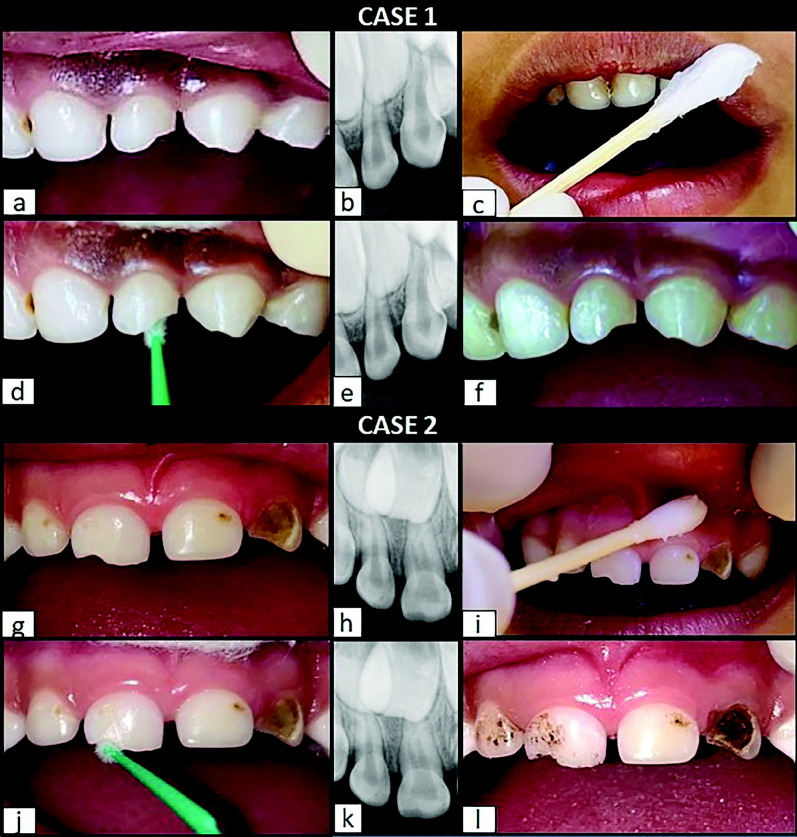

Objective: Dental injury is a significant issue in children due to their immature physical, cognitive, and physiological development. These factors often result in heightened fear and behavioral challenges during their first visit following trauma, which can compromise the quality of treatment and lead to a poor prognosis for the affected tooth. Silver Diamine Fluoride (SDF), a colorless solution approved by the US FDA for treating dental hypersensitivity and caries, offers a simple, painless, and non-invasive treatment option. Its application involves a paint-on technique with a powerful fluoride formulation, making it an ideal choice for the initial management of enamel and dentin fractures in primary teeth, particularly in uncooperative young children.

Case description: This case series described four cases in which SDF was successfully used as the primary treatment for Ellis Class IX anterior tooth trauma in very young children with negative behavior responses in the dental setting. The procedure required minimal armamentarium and was well-tolerated by all patients.

Conclusion: In each case, the use of SDF yielded successful and satisfactory outcomes, with a favorable prognosis for the affected teeth. Additionally, the treatment contributed to a positive shift in the children's attitudes toward dental care.